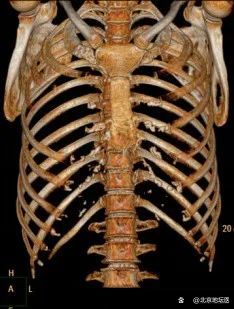

张阿姨入院后,胸外科团队尽快完善了各项术前检查。经胸部CT检查显示,复发的肿瘤位于胸骨下端右侧,与周围组织分界不清,甚至已经侵犯胸骨和临近肋骨。为了确保最好的手术效果,杨龙海副主任带领团队通过认真的术前讨论,并与麻醉科团队经过科学评估,制定了完善的手术计划。

术前检查